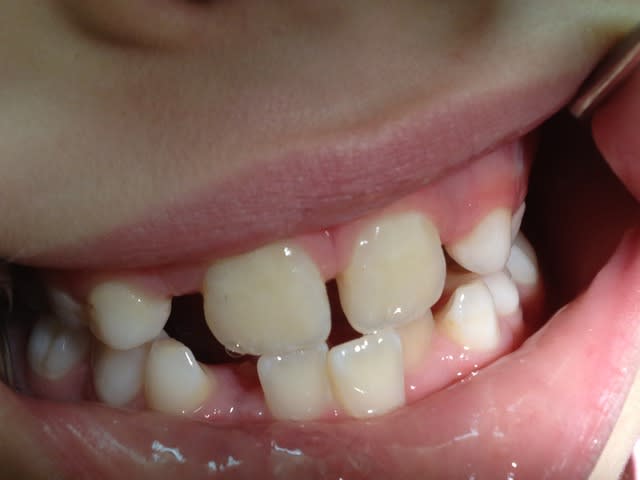

Re!!! Voilà de nouvelles photos, donc pour résumer ,enfant de 7ans auquel l'ortho me demande d'extraire les 4 canines de lait pour laisser la place aux latérales.Probléme ;est ce que l'expansion est possible:Merci de toutes vos réponses

On ne peut pas dire grand chose avec ces photos, tu nous donnes des photos et des radios du secteur antérieur pour qu'on te donne un avis sur ce qui se passe en postérieur... Ce qui aurait été intéressant ça aurait été de voir la forme du palais par exemple ou au moins l'occlusion sur les secteurs latéraux.

Bref, pour faire simple, là on voit pas grand chose, mais j'ai l'impression sur ta 4eme photo que l'occlusion est inversée à droite... 85 semble plus vestibulaire que son antagoniste, non ? Et du peu qu'on en voit en secteur gauche ça semble être du même genre non ? Regarde la forme du palais : s'il te semble creusé et étroit, ça doit te mettre la puce à l'oreille.

La ddm est pas si terrible que ça!

En ce qui me concerne on commencerait pas expansion fonctionnelle, planas, soulet et besombes, orthoclonic, pourquoi pas quad helix si tu trouves pas mieux mais certainement pas extraire.